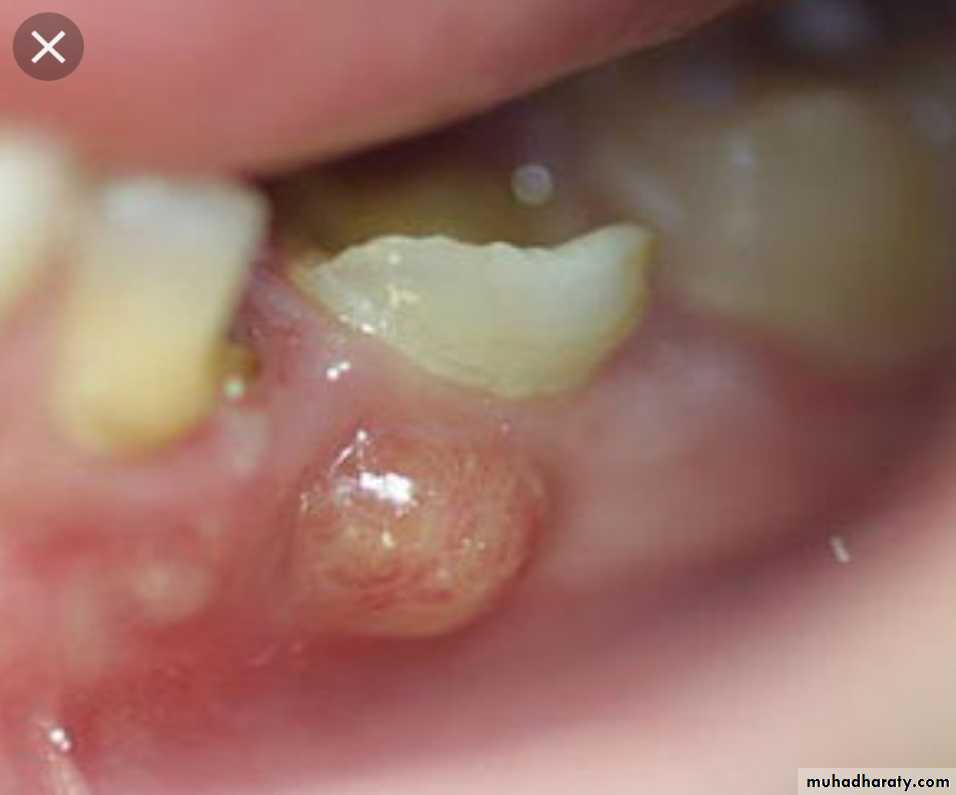

Grossly : a red swollen mass, the middle is filled with pus & debris, surrounding skin appears pink/red